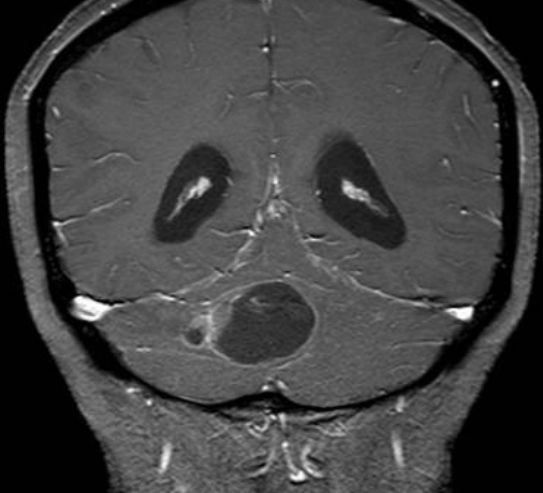

病例6

患儿女性,8岁,反复呕吐半年,3年前有癫痫发作,未诊治。

答案:Sturge-Weber综合征(SWS)。

补充资料:患儿右侧眼眶、颜面部见大片红色斑块,无溃疡。患儿癫痫、呕吐,颅内皮层脑回状钙化,大血管未见畸形,考虑SWS。在没有CT的情况下,本病例诊断存在困难。Sturge-Weber综合征又称脑颜面血管瘤病、脑颜面三叉神经血管瘤病、软脑膜血管瘤病等,是先天性颜面与脑混合性血管畸形,病变的主要特点为面部三叉神经分布区皮肤血管瘤和同侧软脑膜血管瘤。钙化多发生于软脑膜血管瘤下的脑皮质,并可累及整个皮层,但常见于第2~3层。钙化早期位于血管周围,以后位于血管瘤和周围组织之间。钙化有脑回状、斑块状、点状、条状等多种形态,以脑回状为特征。